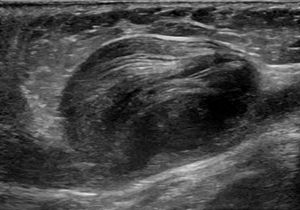

주머니형 동맥류 또는 "베리" 동맥류는 구형이며 혈관벽의 일부만을 포함한다. 일반적으로 직경이 5cm에서 20cm 범위이며, 부분적으로 또는 완전히 혈전으로 채워져 있는 경우가 많다.[3] 주머니형 동맥류는 동맥류를 주요("모체") 동맥에 연결하는 "목"과 돔이라고 하는 더 크고 둥근 영역을 가지고 있다.

진성 동맥류는 동맥벽의 세 층(내막, 중막, 외막) 모두를 포함하는 동맥류이다. 진성 동맥류에는 죽상경화성 동맥류, 매독성 동맥류, 선천성 동맥류뿐만 아니라 관통성 심근 경색 후 발생하는 심실 동맥류도 포함된다(심장벽의 모든 층을 포함하는 동맥류도 진성 동맥류로 간주된다).[3]가성 동맥류(위동맥류)는 동맥 또는 정맥에서 완전히 새어나온 혈액이 주변 조직에 의해 혈관 옆에 국한된 것이다. 이 혈액으로 채워진 공동은 결국 누출을 봉쇄할 만큼 혈전(응고)되거나 주변 조직에서 파열될 것이다.[3]